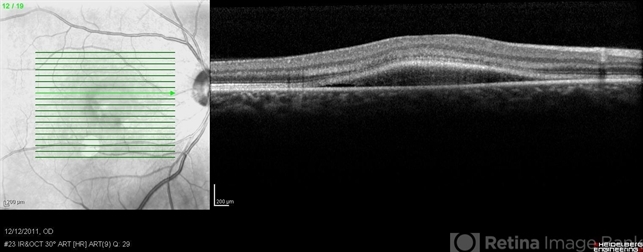

- central serous chorioretinopathy (CSCR), subretinal fluid

- Optical coherence tomography system

- Recurrent central serous with fibrin in a 54-year-old man